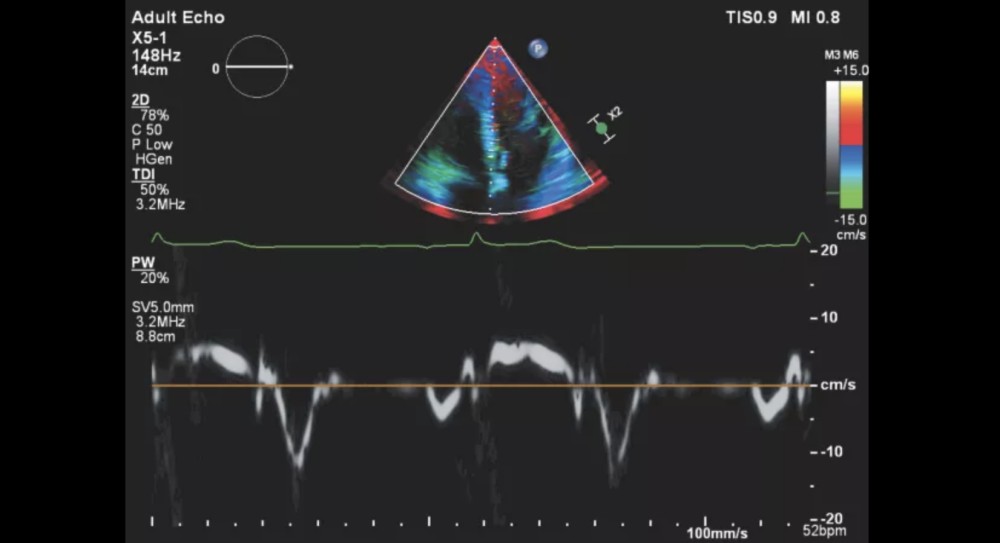

Təkmilləşdirilmiş Görüntüləmə Modalları

Live xPlane imaging, iRotate, Live 3D (3D TEE daxil olmaqla)

X5-1: xMatrix / yetkin eko (2D, Live xPlane)